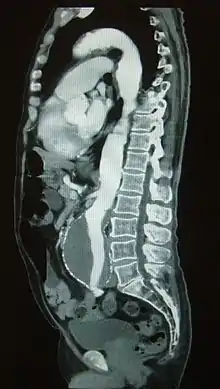

يشخص تمدد الشريان الأبهري البطني عادة بواسطة فحص بدني، أو بمسح الموجات فوق الصوتية، أو بالتصوير المقطعي. قد تظهر صور أشعة البطن الخطوط العريضة لتمدد الأوعية الدموية عندما تكون جدرانه متكلسة. وهذا هو الحال في أقل من نصف حالات تمدد الأوعية الدموية. يستخدم التصوير بالموجات فوق الصوتية للكشف عن تمدد الأوعية الدموية وتحديد حجم أي من الموجود. بالإضافة إلى ذلك، يمكن الكشف عن السائل البريتوني وهى من الوسائل الغير تداخلية وذات حساسية عالية، ولكن وجود الغازات في الأمعاء أو وجود السمنة قد يحد من فائدتها. الاشعة المقطعية ذو حساسية لاكتشاف تمدد الأوعية الدموية ما يقرب من 100 ٪ ومفيد أيضا في التخطيط السابق للجراحة، تفاصيل التشريح وتركيب جسم المريض وإمكانية إصلاح الأوعية الدموية من الداخل. في حالة تمزق التمددالمشتبه به، فإن يمكنه أيضا الكشف عن السوائل خلف البريتون. بدائل قليلا ما تستخدم كأساليب التصوير لتمدد الأوعية الدموية وتشمل التصوير بالرنين المغناطيسي وتصوير الأوعية.

تعزيز الاشعة المقطعية يدل على وجود تمدد الشريان الأورطي البطني ب4.8 بنسبة 3.8 سم